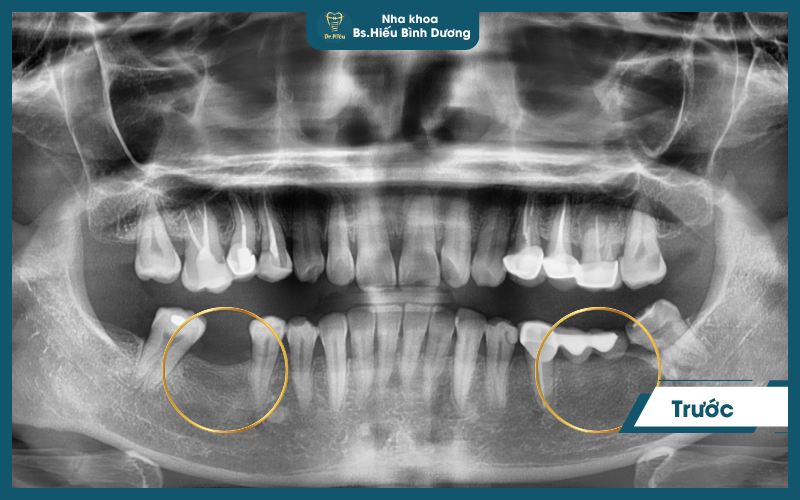

Quy trình chuẩn y khoa

- Thăm khám & chẩn đoán toàn diện bằng CT Cone Beam 3D

- Lập kế hoạch điều trị chính xác

- Cấy trụ Implant trong môi trường vô trùng

- Chờ tích hợp xương 1-3 tháng

- Phục hình răng sứ đúng khớp cắn

- Theo dõi & bảo trì định kỳ 6 tháng/lần